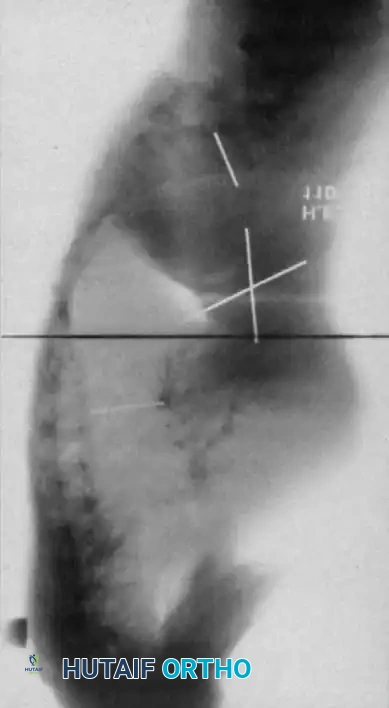

Dystrophic Kyphoscoliosis

Dystrophic scoliosis coupled with angular kyphosis represents one of the most formidable challenges in spine surgery. Patients with this pathology respond exceptionally poorly to posterior fusion alone. Consistent, long-term success is achieved almost exclusively through combined anterior and posterior (360-degree) fusions.

Winter and Hsu emphasized that the primary reasons for failure in these curves are inadequate bone graft volume and insufficient fusion area. The surgical strategy must include:

1. Anterior Release and Corpectomy: The entire structural area of the deformity must be addressed anteriorly. This requires complete, aggressive disc excision back to the posterior longitudinal ligament.

2. Structural Strut Grafting: Strong strut grafts are biomechanically imperative to support the anterior column and prevent kyphotic collapse. Fibular allografts or autografts, supplemented with rib and iliac crest cancellous bone, are standard.

3. Vascularized Rib Grafts: For severe, rigid kyphoscoliotic deformities, vascularized rib graft augmentation (as described by Bradford) provides superior biological healing potential in the hostile, dysplastic environment of the NF-1 spine.

4. Posterior Instrumentation: Following the anterior stage, robust posterior segmental instrumentation and arthrodesis are performed.

Fig. 38-202: Postoperative radiographs demonstrating anterior fusion with vascularized rib graft and structural strut grafting in a patient with severe dystrophic kyphoscoliosis.

For smaller dystrophic kyphoscoliosis (kyphosis <40 degrees), posterior instrumentation and arthrodesis may be attempted early, but the fusion mass must be explored at 6 to 12 months. If kyphosis exceeds 50 degrees, the combined anterior/posterior approach is non-negotiable. The anterior fusion must extend one or two levels beyond the end vertebrae of the kyphotic segment to prevent junctional failure.